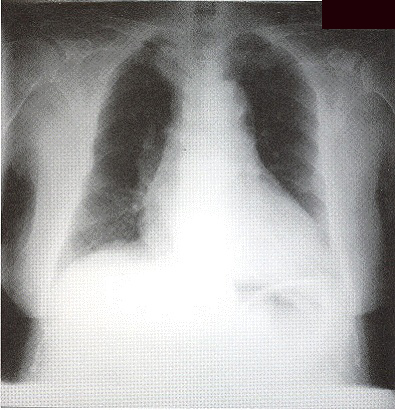

Complete blood picture showed mild neutrophilia. ESR was raised to 123mm/hr. She had mild renal impairment. Arterial blood gas on room air was nonnal on admission. Albumin/globulin ratio was reversed. Liver profile was normal. Sputum for culture grew oral flora and all smears for acid-fast bacilli were negative. CXR (Fig I) showed bilateral patchy opacity with nonnallung volume. No abnonnal mediastinal shadow was found. Old CXR of this patient was nonnal (Fig 2).